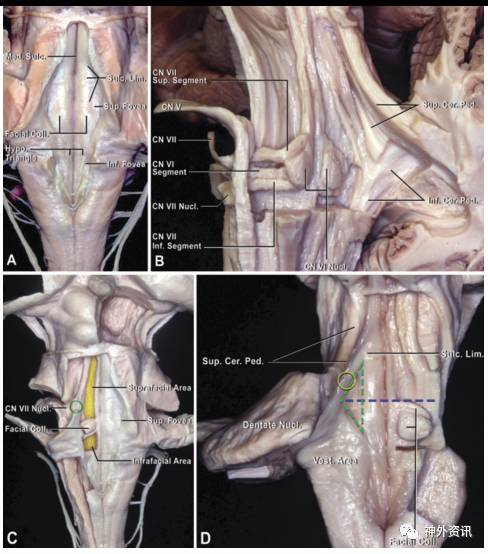

面丘是在脑干背侧的四脑室底面、双侧对称的隆起结构,内含外展神经核和面神经脑干段。上三角凹位于面丘的外侧,其上外侧边由小脑上脚构成,下外侧边邻近前庭区;而内侧边由界沟组成,顶点与面丘的上边位于同一水平(图1)。枕下正中经脉络膜髓帆入路暴露四脑室底面后,可从上三角凹的顶点向前庭区切开,从而进入脑干深部,探查并切除病灶(图2)。

图1. 四脑室底面的上三角凹。A.界沟、外侧沟之间可见凹陷形成的上三角凹;B.面丘由外展神经核、面神经脑干段组成,小脑上脚构成四脑室的上外侧壁,小脑下脚构成四脑室的下外侧壁;C.面丘上方入路和面丘下方入路可用于处理脑干背侧病灶,绿圈所示为三叉神经运动和感觉核;D.界沟在面丘外侧加深并凹陷形成上三角凹,即绿色虚线所标。

图2. 枕下正中经脉络膜髓帆入路。A.枕下正中开颅,切开硬脑膜;B.充分暴露延髓背侧和小脑扁桃体;C.打开小脑扁桃体和蚓垂之间的脑沟(绿色虚线处),暴露和切开脉络膜髓帆连接处后即可进入四脑室;D.四脑室底部双侧隆起即为面丘,切开上三角凹的后半部分(红线处)。